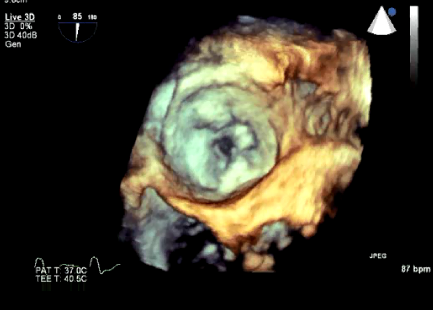

Curso de ecografía crítica en todas sus modalidades (ecocardiografía transtorácica y transesofágica, ecografía pulmonar, vascular, cerebral, FAST) dirigido a: médicos intensivistas, emergenciólogos, anestesiólogos, internistas, médicos de familia, neumólogos, cardiólogos y a todo aquel interesado por utilizar la ecografía como parte del examen físico del paciente crítico.

Nociones básicas sobre el análisis de la deformidad miocárdica por Speckle Tracking y su utilidad en críticos y muchas cosas más.

En nuestro afán por seguir el trabajo empezado hace ya varios años desde Europa (España) por impulsar la ecografía crítica para intensivistas, emergenciólogos, anestesistas, internistas, subespecialistas de obstetricia crítica, neumólogos y todo aquel médico interesado en aprender a utilizar la ecografía como parte de su examen físico, ahora desde Centroamérica (Panamá), hemos escrito el primer libro Latinoamericano-Europeo de ecografía crítica sub-especializado y dedicado exclusivamente al paciente con shock de cualquier etiología (obstructivo, distributivo, cardiogénico, hipovolémico) que involucra todas las modalidades ecográficas: ecocardiografía, ecografía pulmonar, vascular, abdominal, del sistema nervioso central/doppler transcraneal, etc) en el que participan muchos expertos en sus respectivas áreas tanto de Europa como de América y también algunos profesores del EDEC (Diploma Europeo de ecocardiografía / ESCIM- Sociedad Europea de Medicina intensiva).